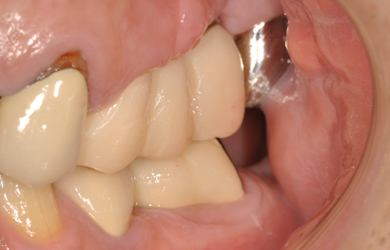

骨再生インプラント治療+セラミック治療

| カテゴリー | 【インプラント治療】【セラミック治療】 | ||||||||||||||||||||||||||||||||

| 治療方針 | ソケットリフト法により上顎洞底部を挙上することにより、骨の無い部分に骨をつくってあげ、インプラント治療を可能にする。 | ||||||||||||||||||||||||||||||||

| 治療内容 | インプラント2本(ソケットリフト)、メタルボンドセラミック5本、ハイブリッドセラミック2本 | ||||||||||||||||||||||||||||||||

| 総治療費 | 1,355,300円 | ||||||||||||||||||||||||||||||||

| 治療期間 | 海外から9ヶ月 |